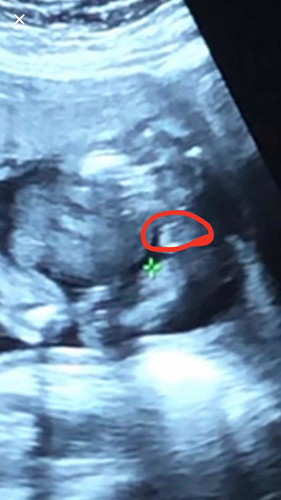

แบบนี้ผู้หญิงหรือชายค่ะ หมอบอกผู้ชายค่ะ

แม่ดูรูปไม่ค่อยเป็นค่ะ

น่าจะ..ญ